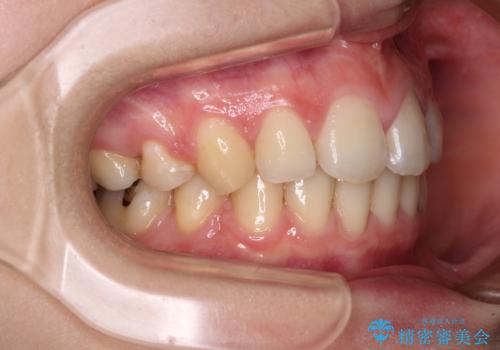

- 口元の突出感と口の閉じにくさを気にして来院された患者様です。

上下左右第一小臼歯4本を抜歯し、ワイヤー装置にて口元を引っ込めるよう矯正治療を行うこととしました。

ご友人などがびっくりするほど口元の突出感を改善することができ、患者様には大変満足していただきました。